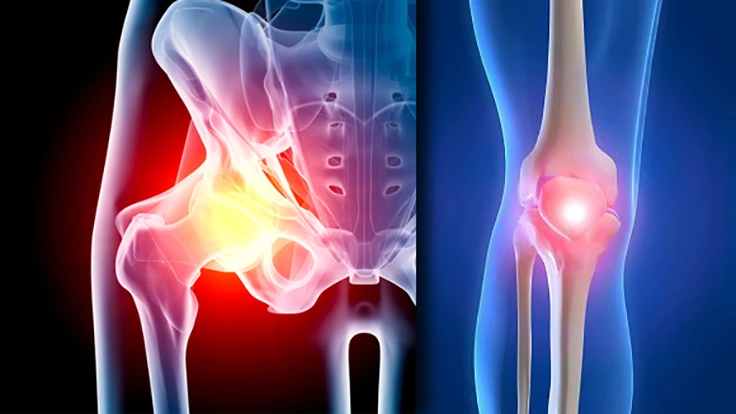

Albany, New York – Older people have trouble making their joints last as long as they do. The patient stability and the relief from pain provided by the implant is compelling. The major suppliers are providing implants that are state of the art. Orthopedic reconstructive implants are used to replace joints that have deteriorated. Deterioration may come as a result of aging, disease, osteoarthritis, or injury.

Reconstructive joint surgery involves the modification of the affected area of the joint and the implantation of one or more manufactured components. It may involve the use of bone cement. The primary orthopedic reconstructive targets are joints. Hips and knees are the joints most commonly repaired with orthopedic implants.

Implant assisted medial knee arthroplasty: orthopedic surgical implants are poised to take knee and hip surgery quality far beyond what has previously been available. The quality of knee arthroplasty is improved with implant capability. All the advantages of surgical implants carry into the orthopedic reconstruction surgical products. When the knee and hip surgical implants are used, patients have reduction of post-operative pain, fewer re-admissions to hospital and faster recovery. Implants support high-precision surgery.

Knee and hip surgical implants need robots to provide consistent reproducible precision. Knee or hip replacement will demand attention to quality of life. Maintenance of lifestyle provided by an implant as a joint replacement is compelling. As next generation systems, hip and knee implants provide a way to improve traditional orthopedic hip and knee replacement surgery. Total hip replacement surgery has evolved dramatically as advances in technology have brought improved surgical techniques. Surgical implants are a significant part of that advance.